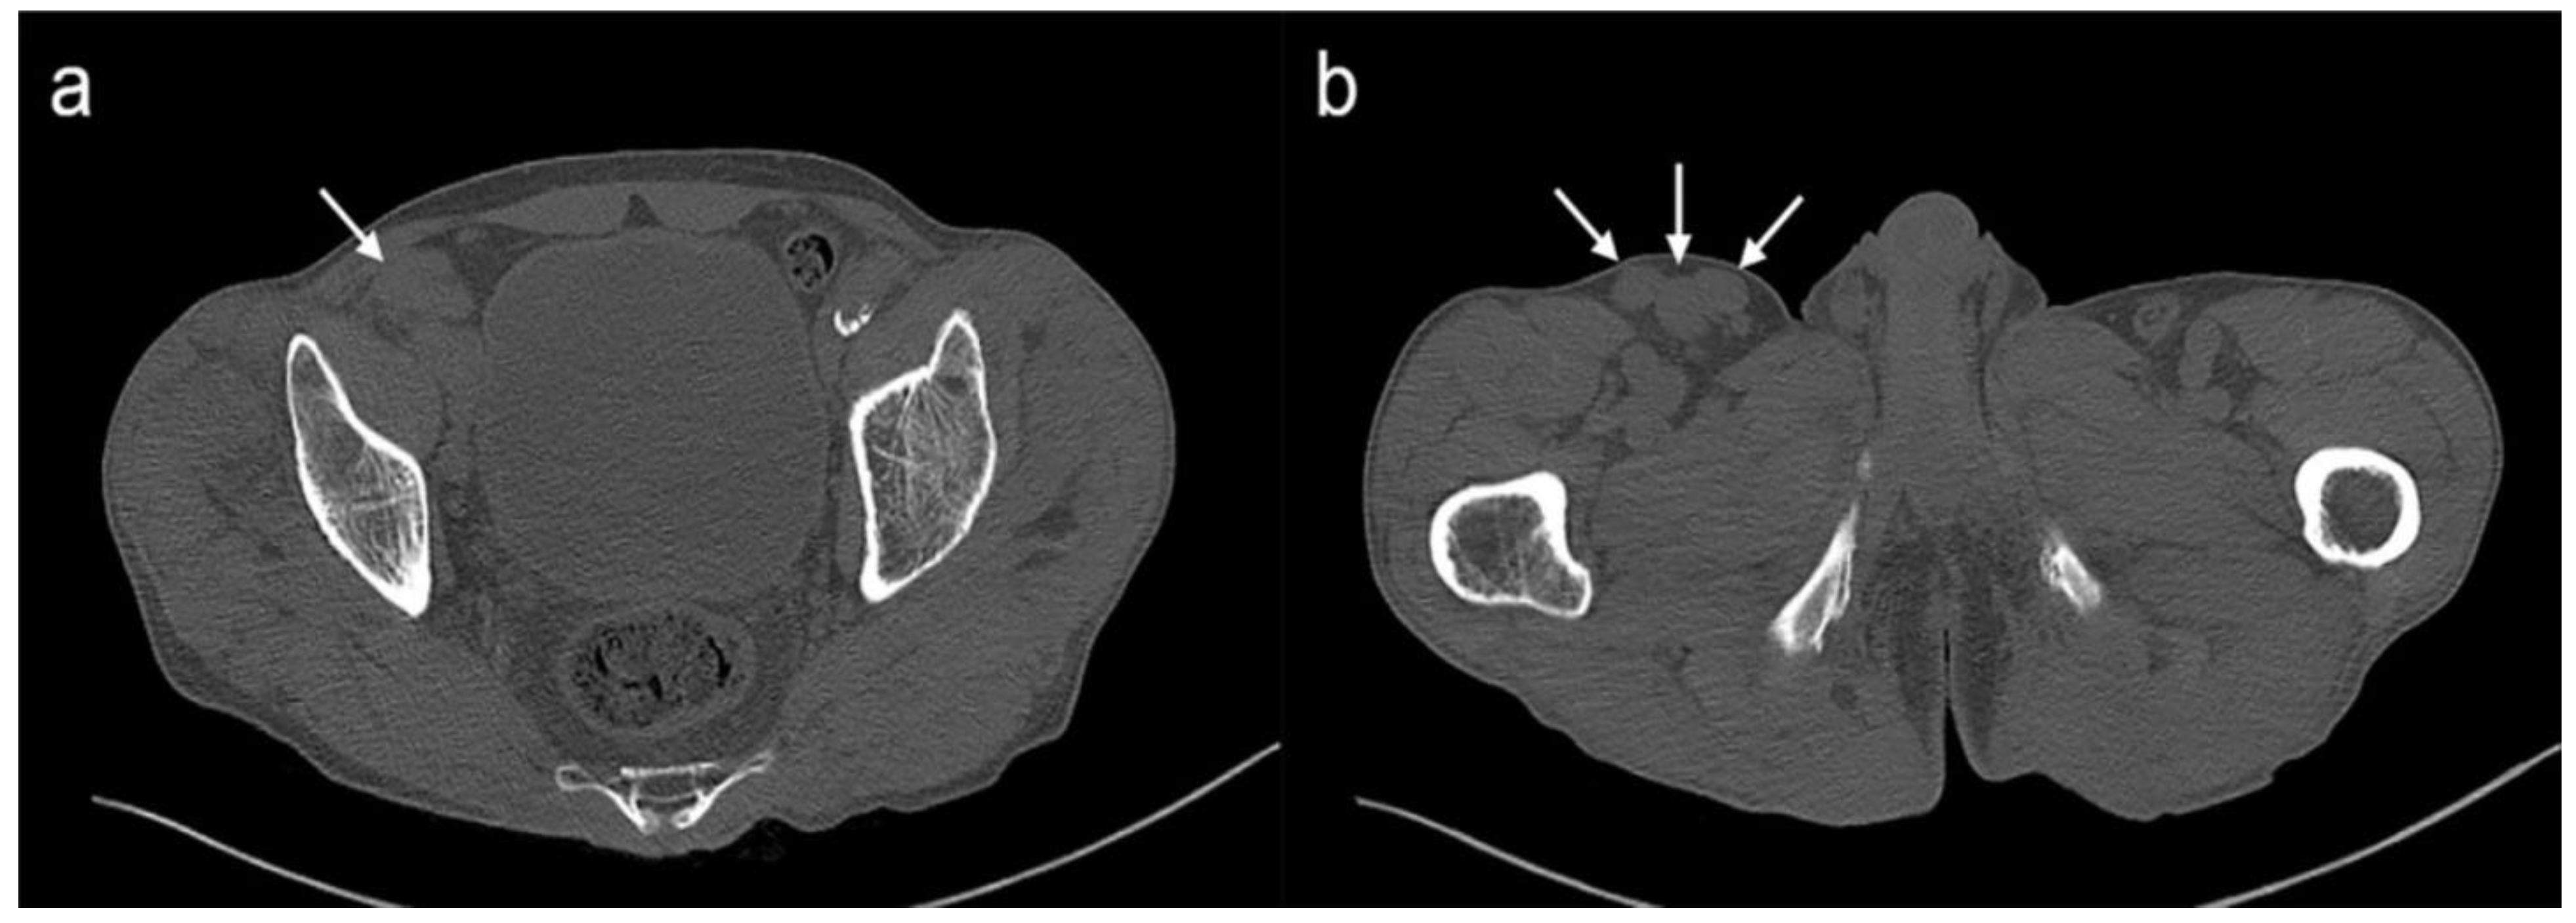

2. Case Report